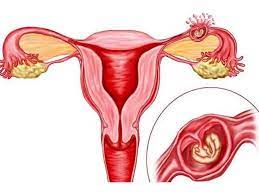

قیمت: 48٬000 تومان - دسته بندی فایل: علوم پزشکیپاورپوینت حاملگی خارج رحمی

فروش ویژه پاورپوینت حرفه ای حاملگی خارج رحمی با تخفیف استثنایی فقط 69 هزار تومان تعداد اسلاید : 44 اسلاید